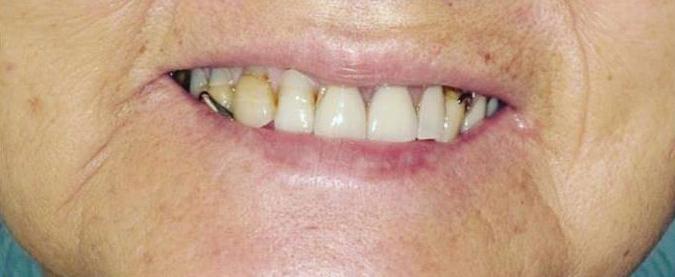

Pediatric Partial Denture to Replace Missing Teeth

Strengthening Smiles

Understanding the Importance Of Splinting Periodontally Involved Teeth

By Marc P. Stanard, DDS, PC

Periodontal disease affects millions worldwide, jeopardizing not just the health of teeth but the overall well-being of individuals. Among the treatment modalities available, splinting of periodontally involved teeth emerges as a significant strategy in preserving dental health and function. Splinting involves bonding multiple teeth together to provide stability and support, thereby preventing further damage and facilitating healing.

Understanding the role and benefits of splinting is crucial for both patients and dental professionals in combating periodontal disease effectively.

Periodontal disease, characterized by inflammation and infection of the gums and surrounding tissues, often leads to tooth mobility— a distressing symptom indicating significant tissue and bone loss. Tooth mobility not only affects chewing and speaking but also poses a threat of tooth loss if left untreated. Splinting offers a solution by redistributing forces among the connected teeth, reducing individual tooth stress and enhancing overall stability.

The process of splinting begins with a comprehensive assessment of the patient’s periodontal condition. Once the severity of mobility and bone loss is determined, suitable splinting techniques are chosen. Common methods include using

wires, resin materials, or a combination of both to connect the affected teeth. These splints can be temporary or permanent, depending on the patient’s needs and the clinician’s recommendation.

One of the primary benefits of splinting is its ability to preserve natural dentition. By stabilizing mobile teeth, splints prevent further movement, allowing the periodontal tissues to heal. This not only improves the functionality of the teeth but also enhances the patient’s quality of life, restoring confidence in their smile.

Moreover, splinting aids in maintaining proper occlusion—the alignment of teeth when the jaw is closed. By preventing excessive movement of periodontally involved teeth, splints help preserve occlusal stability, preventing complications such as TMJ disorders and premature wear of teeth.

For patients undergoing peri-

odontal treatment, understanding the importance of splinting is essential. While it may seem daunting at first, splinting offers a promising solution for stabilizing compromised teeth and preventing further deterioration. However, proper oral hygiene practices, including regular brushing, flossing, and professional cleanings, remain integral in maintaining the longevity of splinted teeth.

Splinting of periodontally involved teeth serves as a valuable tool in the management of periodontal disease. By providing stability, preserving dentition, and maintaining occlusal harmony, splints contribute significantly to improving oral health and restoring smiles. Consulting with a knowledgeable dental professional can help individuals make informed decisions regarding their periodontal treatment, ensuring a brighter, healthier future for their teeth and gums.